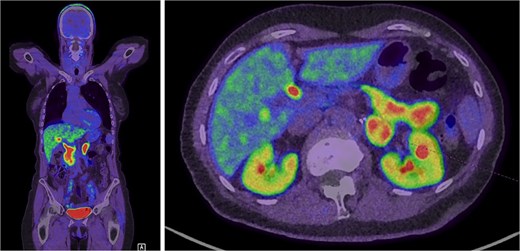

Further evaluation was done to exclude paragangliomas and distant metastases. F-Fluorodopa (FDOPA) positron emission tomography (PET) was performed and showed strong avidity in the lesion suggesting a catecholamine-producing tumour (Fig. 3). She was referred for consideration of a left adrenalectomy. Preoperative preparation with alpha-blockade (Prazosin) was commenced and 17 gene panel testing was negative for a pathogenic variant.

Intense FDOPA uptake is demonstrated in the left adrenal lesion, which is in keeping with a catecholamine-secreting tumour.